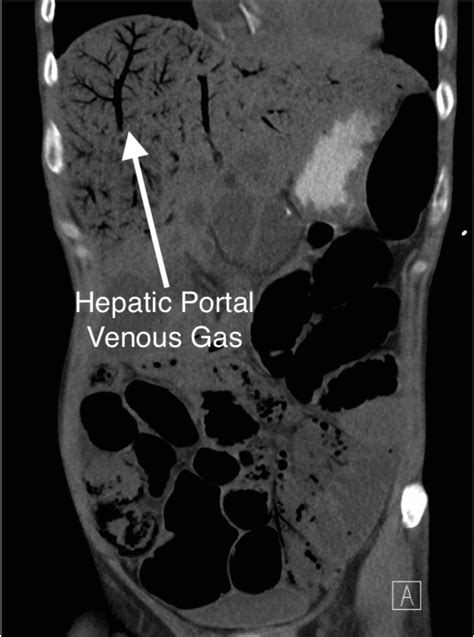

The gold standard for detecting portal venous gas is a CT scan of the abdomen, usually with intravenous contrast. On a scan, gas appears as low-attenuation, branching, linear lucencies that extend into the periphery of the liver. This pattern is distinct from pneumobilia (gas in the bile ducts), which typically resides in the central portion of the liver and follows the path of the biliary tree.

Distribution Extends to the liver periphery Central, follows biliary tree

Morphology Branching, thin lucencies More rounded, central